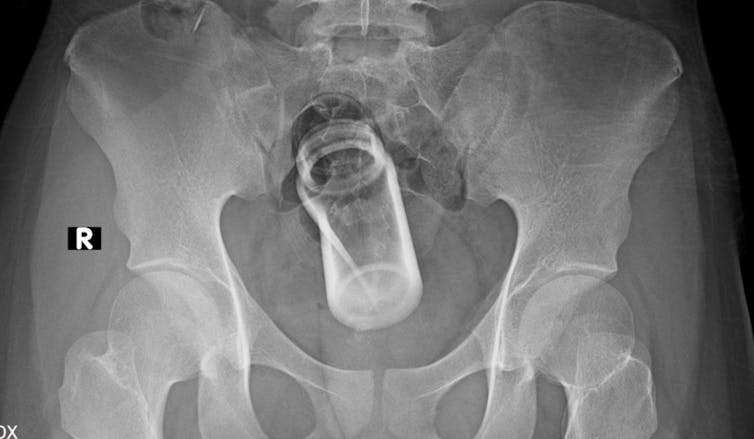

At this end of the body, there are also things found in the anus and rectum. Between 66% and 85% of those attending A&E with this complaint are men.

One of the biggest issues with foreign objects in the anus and rectum is they can become lodged, blocking the natural movement of intestinal contents. Over time, this can cause significant stretching of the tract and runs the risk of perforating or tearing the bowels.

There are many reasons people put foreign objects up their anus, ranging from the more common erotic reasons to the less common constipation relief.

While the reasons are diverse, they are surpassed by the variety of objects found at this end, including: apples, aubergine, brush, pens, carrots, pesticide containers, deodorant can (which represents a fire hazard during surgical removal), drinking glass, fizzy drinks bottles, baseball and probably most eye-watering is a whole coconut.

The issue with rectal foreign bodies is that the sphincters that keep your faeces inside, will do the same to objects that are pushed beyond them, many of which stretch the muscle wall of the rectum to the point where it cannot generate enough force to push the object back outside, meaning surgeons usually have to open the patient up to retrieve the item.